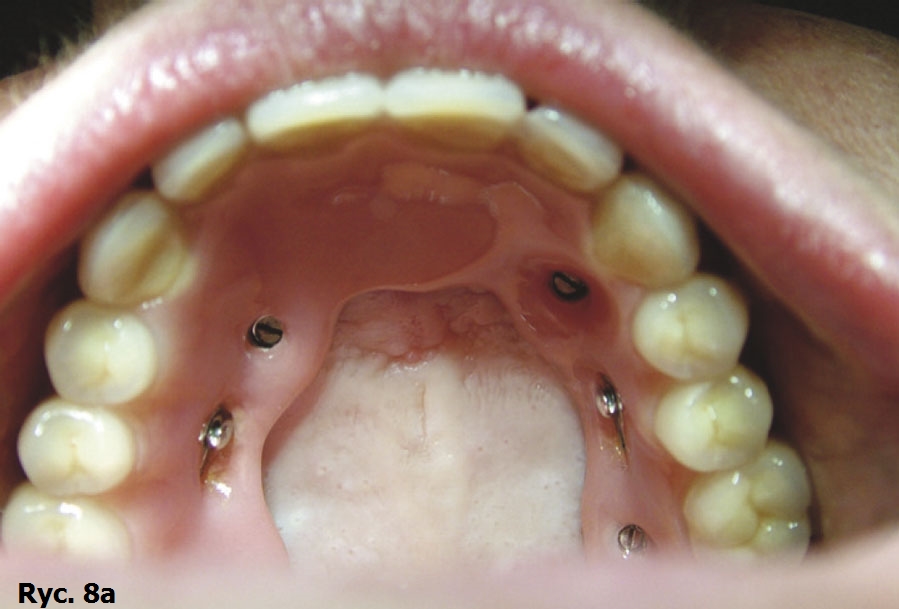

Pacjentka wyraża zgodę na zabieg chirurgiczny, polegający na wprowadzeniu wszczepów podokostnowych, zdając sobie sprawę, że jest to ostatnia deska ratunku, umożliwiająca stabilne zakotwiczenie protezy wspartej na wszczepach. Po zabiegu implantacji dwie oddzielne siatki podokostnowe (ryc. 3) zostaną ze sobą połączone (ryc. 4). Podniesiony płat śluzówkowo okostnowy (ryc. 5) ukazuje zgodność anatomii tkanki kostnej z modelem stereolitograficznym. Pozabiegowe zdjęcie pantomograficzne (ryc. 6) obrazuje idealne połączenie między dwiema siatkami, umieszczonymi precyzyjnie na swoim miejscu. Mezostruktura (ryc. 7) jest odpowiednim podparciem dla docelowej protezy typu „U” (ryc. 8).

Wszczepy podokostnowe - przypadek 1 (ryciny)